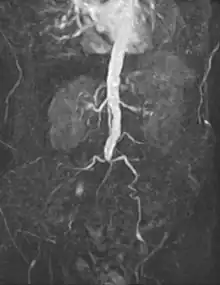

Vascular surgery is a surgical subspecialty in which vascular diseases involving the arteries, veins, or lymphatic vessels, are managed by medical therapy, minimally-invasive catheter procedures and surgical reconstruction. The specialty evolved from general and cardiovascular surgery where it refined the management of just the vessels, no longer treating the heart or other organs. Modern vascular surgery includes open surgery techniques, endovascular (minimally invasive) techniques and medical management of vascular diseases - unlike the parent specialities. The vascular surgeon is trained in the diagnosis and management of diseases affecting all parts of the vascular system excluding the coronaries and intracranial vasculature. Vascular surgeons also are called to assist other physicians to carry out surgery near vessels, or to salvage vascular injuries that include hemorrhage control, dissection, occlusion or simply for safe exposure of vascular structures.[1]

An abdominal aortic aneurysm (AAA) refers to aneurysmal dilation of the aorta confined to the abdominal cavity. Most commonly, aneurysms are asymptomatic and located in the infrarenal position. Often, they are discovered incidentally or on screening exams in patients with risk factors such as a history of smoking. Patients with aneurysms which have a diameter less than 5 cm are at <1% rupture risk per year. When the aneurysm meets size criteria it can be treated with aortic replacement or EVAR.